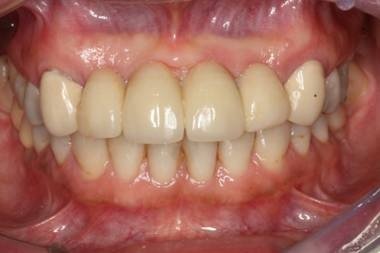

Imagem do artigo

Figura 1. Vista clínica do sorriso intra-oral do paciente durante a consulta de manutenção dos implantes. (8 anos em função)